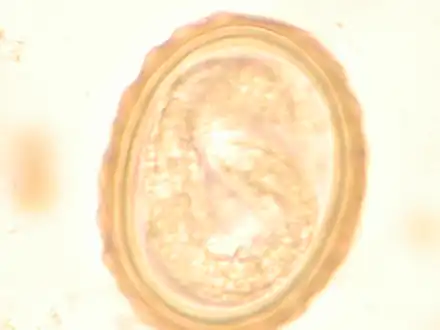

Ascaris egg, incubation process: The Ascaris egg incubation process consists of placing the egg in a controlled environment, at 26 °C (79 °F) during 28 days, in acidic conditions. This process allows for the evaluation of an egg to determine if it is viable or not.

Most diagnoses are made by identifying the appearance of the worm or eggs in feces. Due to the large quantity of eggs laid, diagnosis can generally be made using only one or two fecal smears.[31] The diagnosis is usually incidental when the host passes a worm in the stool or vomit. The eggs can be seen in a smear of fresh feces examined on a glass slide under a microscope and there are various techniques to concentrate them first or increase their visibility, such as the ether sedimentation method or the Kato technique. The eggs have a characteristic shape: they are oval with a thick, mamillated shell (covered with rounded mounds or lumps), measuring 35–50 micrometer in diameter and 40–70 in length. During pulmonary disease, larvae may be found in fluids aspirated from the lungs. White blood cell counts may demonstrate peripheral eosinophilia; this is common in many parasitic infections and is not specific to ascariasis. On X-ray, 15–35 cm long filling defects, sometimes with whirled appearance (bolus of worms).